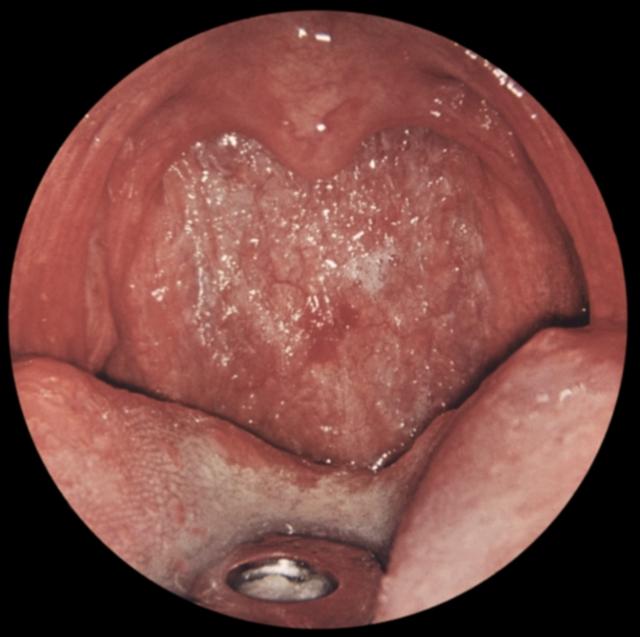

Рис. д). Вид зева при хроническом атрофическом фарингите.